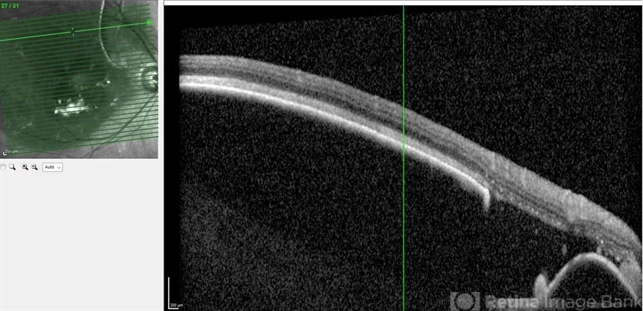

- pigment epithelial detachment (PED), RPE-rip

- Optical coherence tomography system

- OCT image of PED with RPE-rip in 85 year-old male with history of AMD.